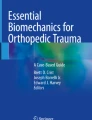

We have demonstrated high rates of union when treating periarticular fractures, complex deformity correction of nonunions and malunions, and limb lengthening and bone transport using multiple divergent pin circular frames [26–29] (Fig. 1). However, the exact orientation of pin placement and optimum number of pins is not known at this time.

(A) A divergent half pin frame using three 6-mm half pins above and below the nonunion is shown. Note each pin is divergent in both the coronal and sagittal planes allowing for simplified frame application. (B) This frame avoids the potential for pin/strut impingement as a minimum of fixation points are mounted to the frame and thus allows maximum excursion of the adjustment struts.